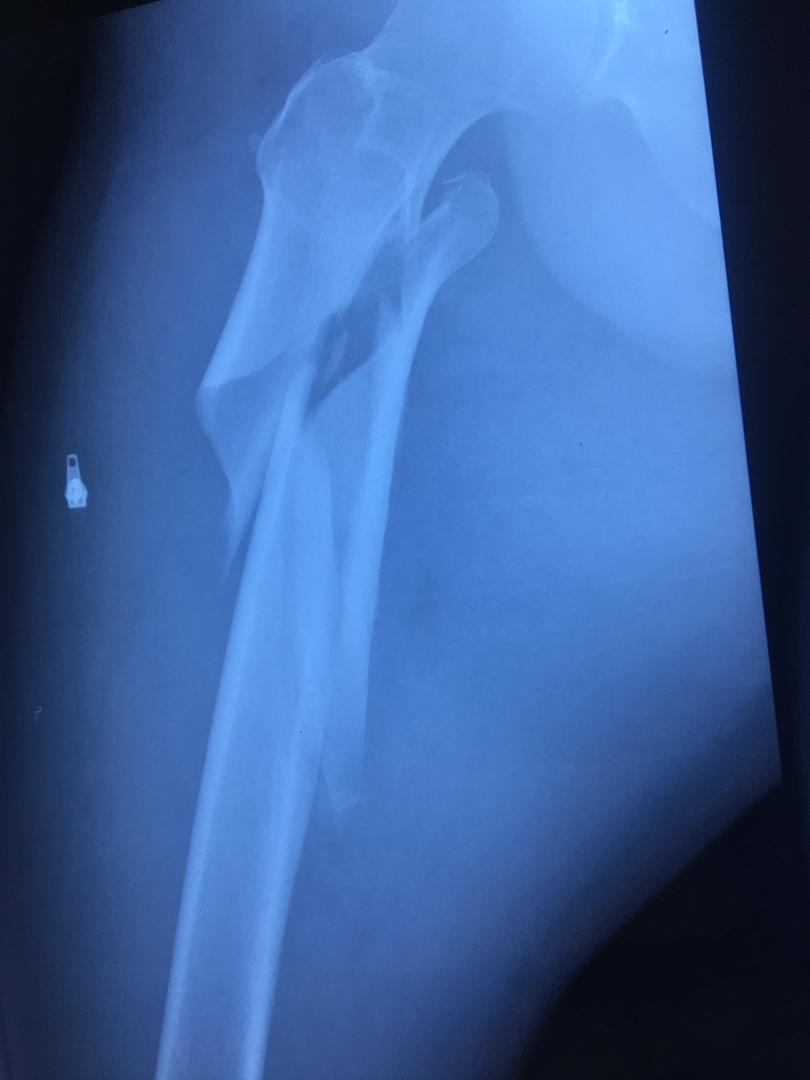

اقای 50 ساله با شکستگی خرد شده ی ران که جراحی و بهبودی کامل